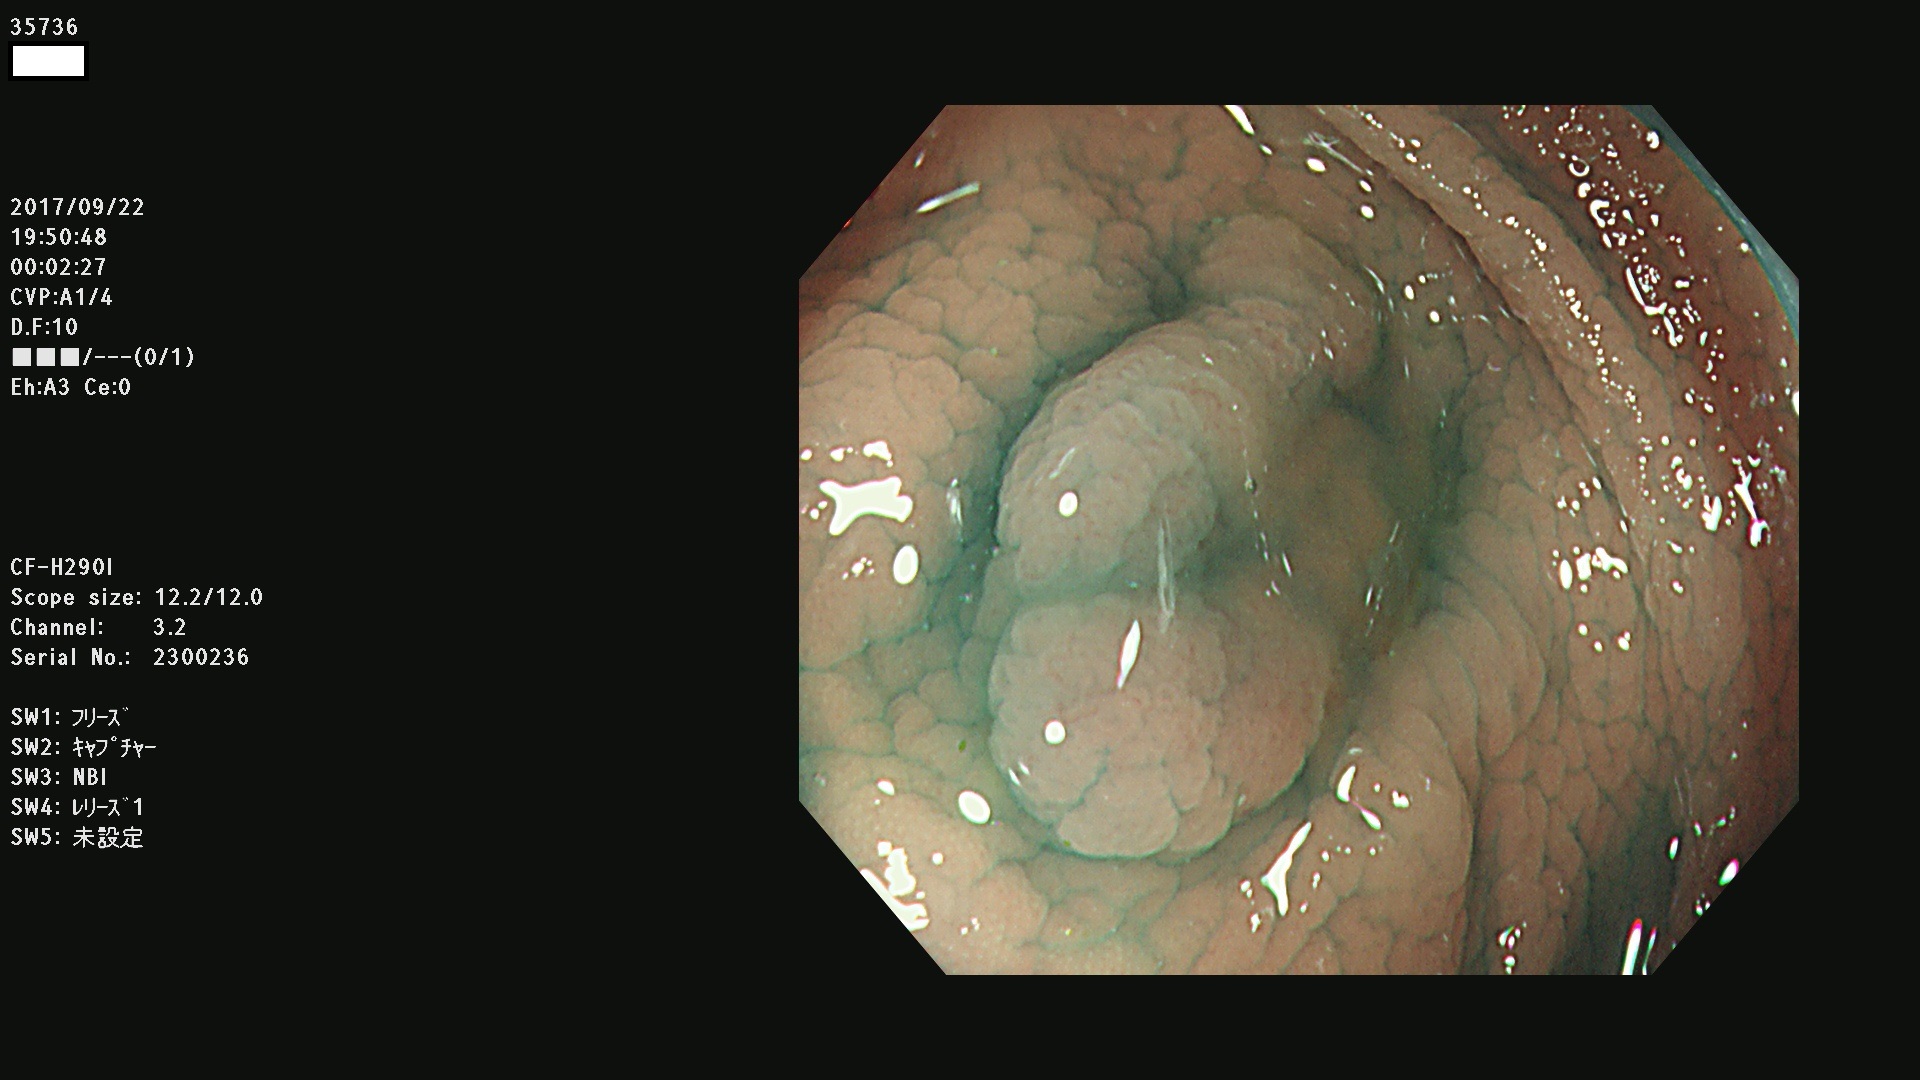

35700 35701 35704 35706 35707 35708 35709 35711(SSA/Pのみ) 35715 35716 35717 35718 35720(SSA/Pのみ) 35722 3576(SSA/Pのみ) 35730 35732 35734(SSA/Pのみ) 35736(SSA/Pのみ) 35741 35742 35743 35744 35746 35748 35749(SSA/Pのみ)35755 35757 35760 35761 35762 35763 35764 35766 35767 35770 35772(SSA/Pのみ) 35773 35781 35783 35785 35786 35787 35788 35791 35795 35796 35797 35798 35799

発見困難で危険性の高い平坦型病変(上記100名より抽出)